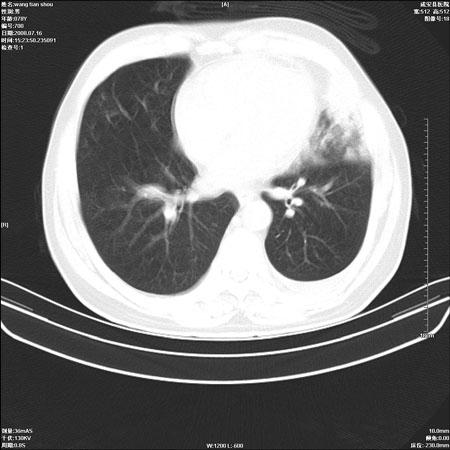

以下是引用qingjing在2008-7-16 19:55:00的发言:[br]1、左上肺不张并堵塞性炎症,建议支气管镜详查;[br]2、左侧胸腔少量积液。

以下是引用wzr在2008-7-16 20:26:00的发言:[br]左肺肺不张伴阻塞性肺炎!另:左侧胸腔少量积液。建议纤支镜检查!